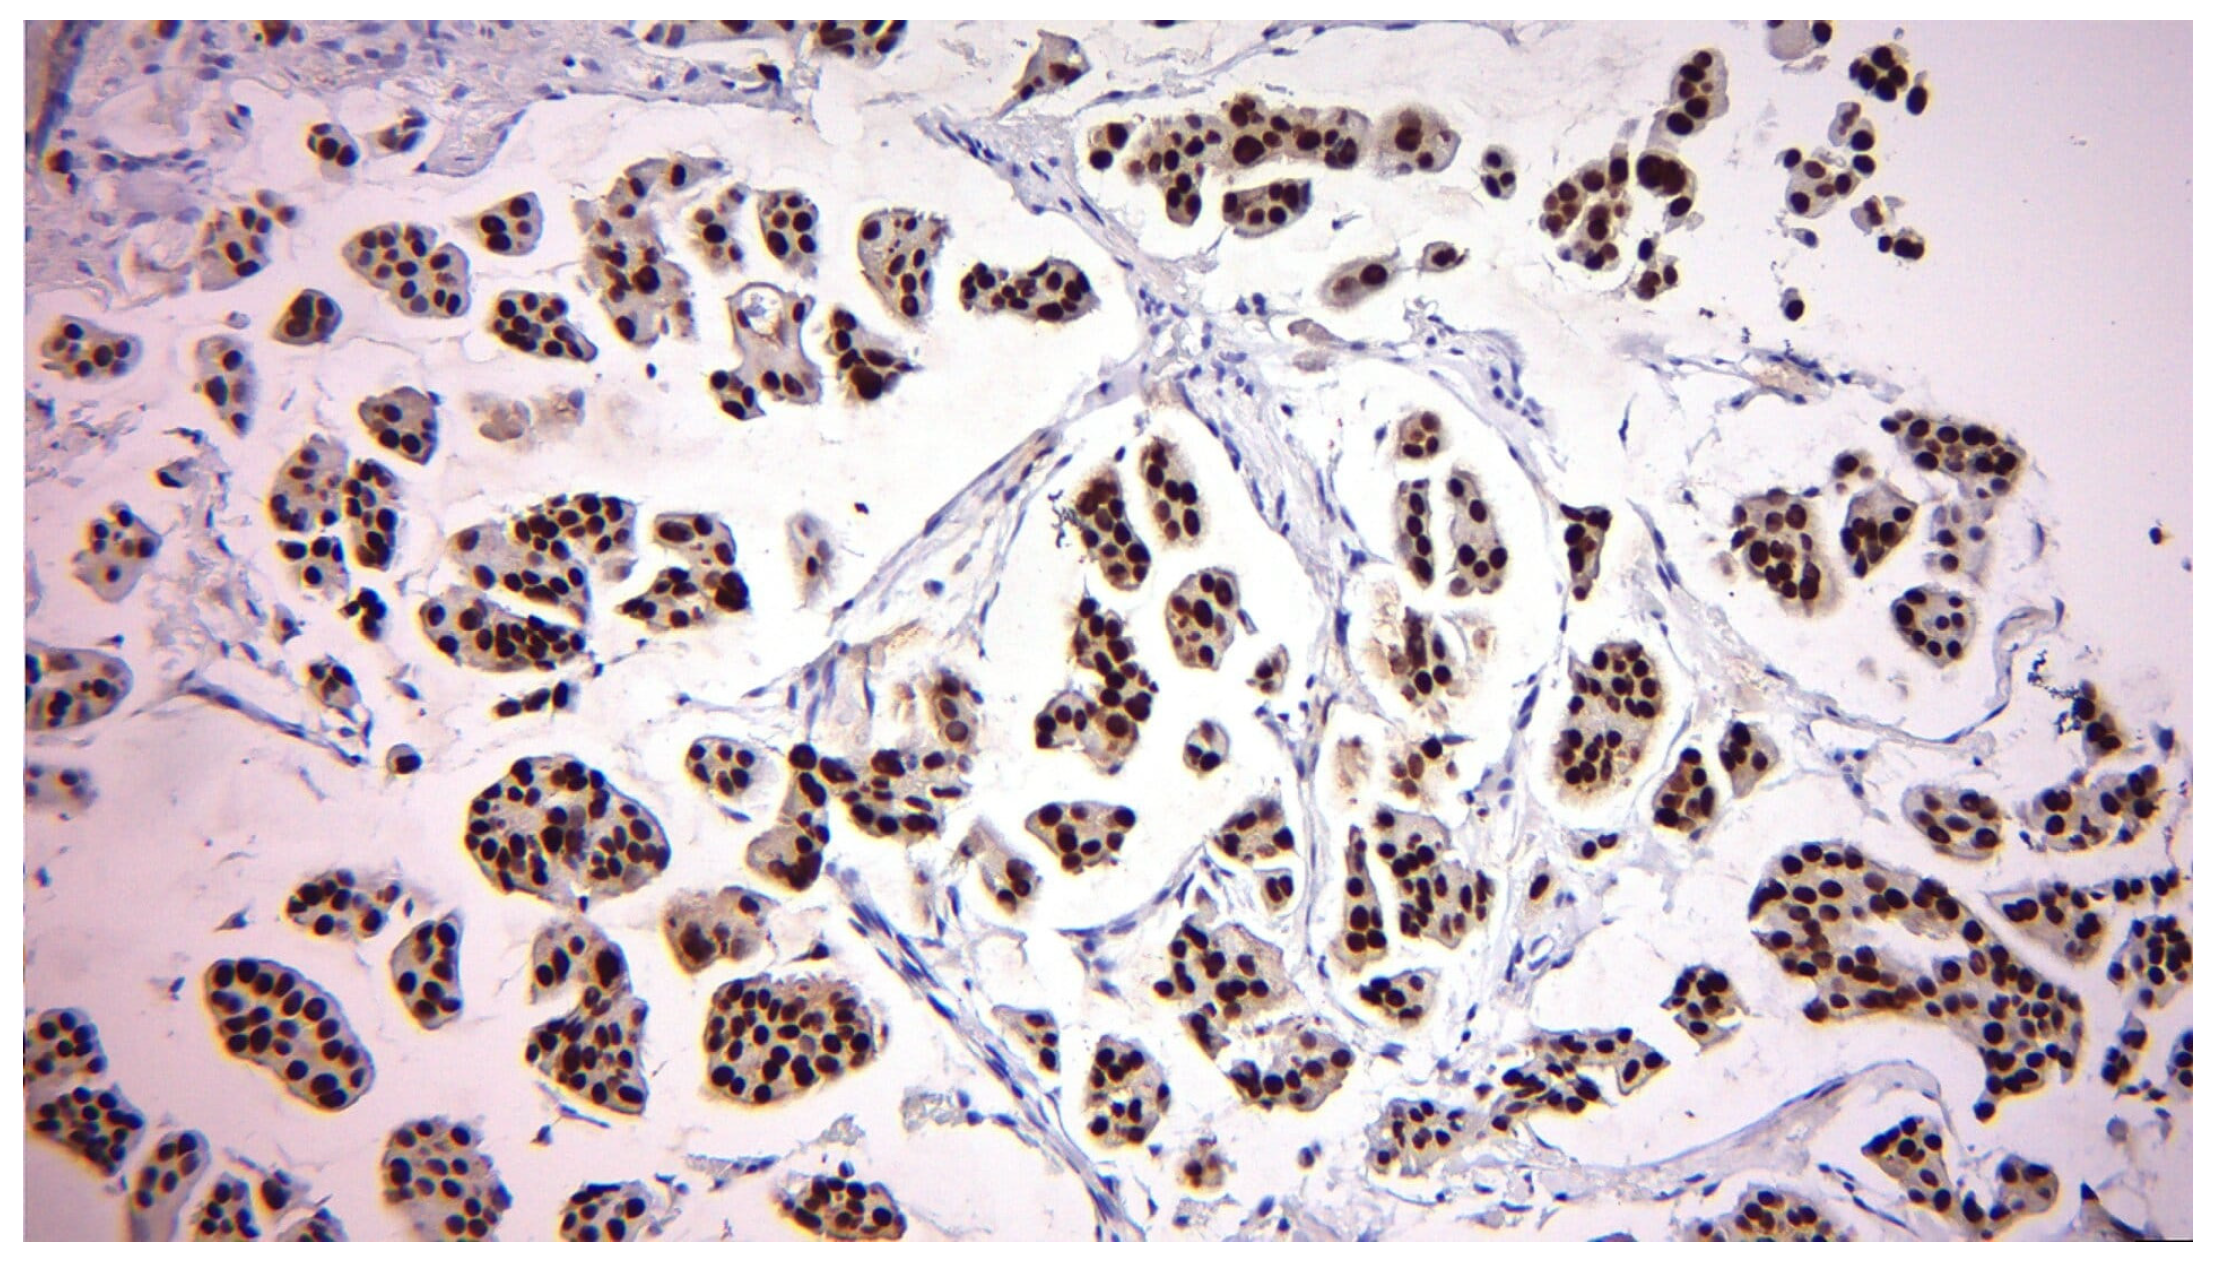

2.3. Biomarker Assessment

3.2.4. Correlation Between Pre-Surgery and Post-Surgery Ki-67